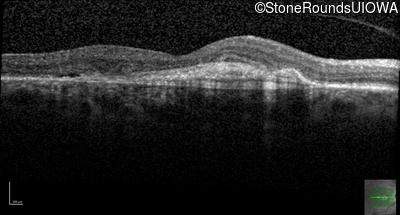

Age at visit: 59 years (Visit 3)